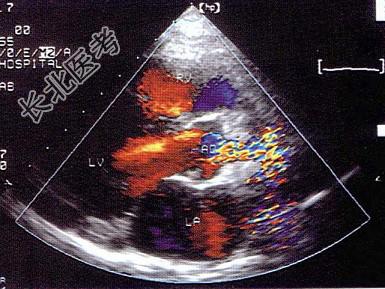

- 单项选择题该病例最可能的诊断为 ( )

A、主动脉瓣上膜性狭窄

B、主动脉瓣上缩窄

C、肥厚性心肌病

D、瓣上环形狭窄

E、高血压病